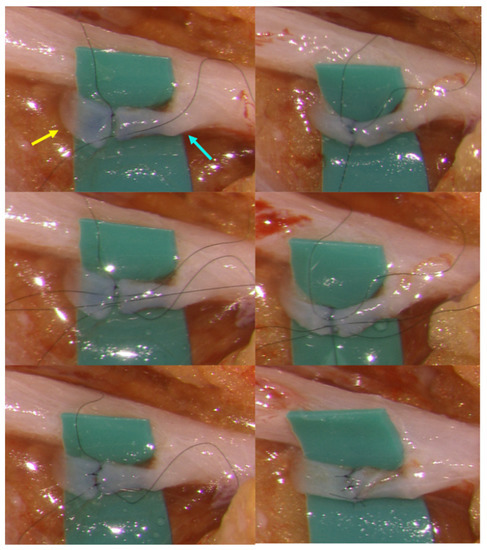

2.2.2. Suture-Stent Technique